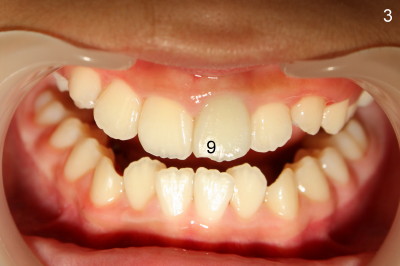

Initial exam shows that the crown of the tooth #8 is slightly discolored (not photographed) and #9 slightly labially shifted with mesioincisal edge chip.  There is no percussion, palpation pain or fistula associated with #8 or 9.  Pulpal vitality test (Endoice) shows that the teeth are reduced in response as compared to #7 and 10.  Pre-op PA shows that #8 canal is obliterated, whereas that of #9 is wide with open apex and + periapical radiolucency (Fig.1).

Two months later (September 03, 2011), the tooth #9 is found to be slightly discolored (Fig.3,4).